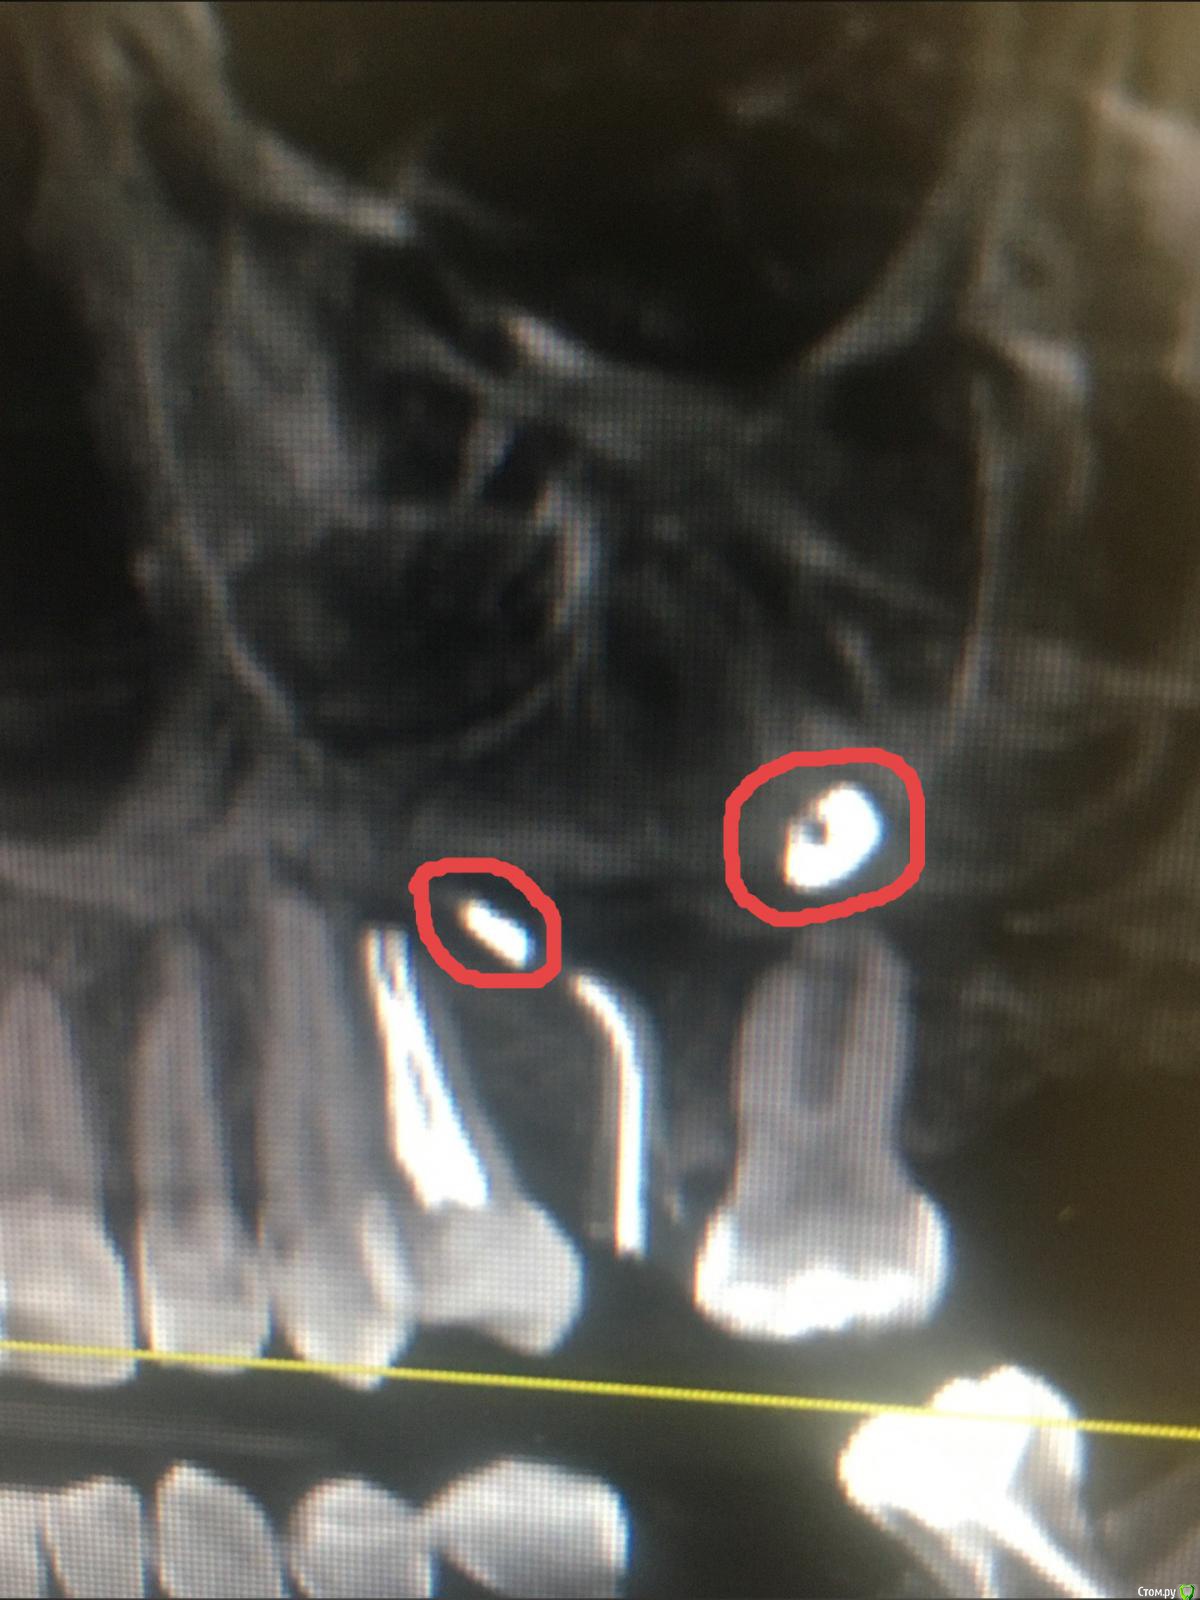

967 Опубликовано 27 февраля, 2020 Поделиться Опубликовано 27 февраля, 2020 Уважаемые коллеги обратилась пациентка, 3 года назад было эндо 25 зуба с выводом материала в пазуху, через год с ее слов начался синусит, проходила лечение у лора, нюансы лечения не знаю, но в итоге лор направил к стоматологу на удаление причинного зуба, далее вопрос от пациентки можно ли удалить из пазухи инородные тела сразу с удалением зуба, я ответил что могу только удалить зуб, в пазухе работать не буду, каким способом устранить проблемы в пазухе? удалить зуб и направить после к лору на эндоскопию, или же вообще не браться за удаление, отправить в члх для удаления вместе с ревизией пазухи? пациентка уже обходила несколько клиник не получив толком ответа, хотелось бы выбрать верную тактику, на данный момент радикс 25 зуба без симптоматики, кт пациентка принесла свое, такую программу я первый раз увидел, поэтому за качество снимков пока извиняюсь, направлю на другое кт по необходимости Ссылка на комментарий

967 Опубликовано 28 февраля, 2020 Автор Поделиться Опубликовано 28 февраля, 2020 Я правильно понял что там корень остался? Достаньте сперва его. Потом к лор-ам по показаниям.это не корень, это силер, просто по снимку так кажется, в обл 25 силер не далеко от апекса, над 26 зубом инородное тело, не похожее на силер, хотя возможно и он мигрировал, но это все надо оттуда удалить желательно малоинвазивно, из ответов выше я склоняюсь все таки к лору, так что спасибо коллеги за ваши ответы Ссылка на комментарий